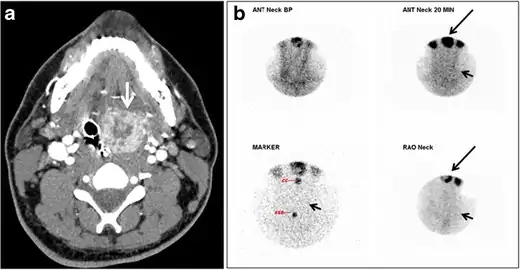

Fig. 22. A 26-year-old male patient with elevated serum parathyroid hormones and calcium secondary to intra-thyroid parathyroid adenoma. a, b Enhanced axial and coronal CT scan of the neck demonstrate a well-defined hypodense right thyroid nodule (white arrows). c Bone window coronal CT scan shows lytic expansile lesions at the right mandible and left frontal bone (white arrows). d Transverse colour Doppler ultrasound of the neck demonstrates a well-defined, heterogonous, predominantly hypoechoic right thyroid nodule measuring 2.7 cm, with mild increased vascularity and no internal micro-calcifications (white arrow). e, f Delayed anterior planar and fused SPECT/CT parathyroid Sestamibi scan at 2 hours demonstrate persistent focal activity in the right thyroid lobe (white arrows). Note the scattered mandibular/maxillary uptakes in planar image representing the known brown tumours.[1]